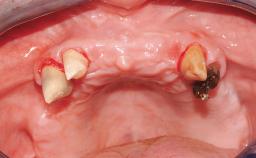

Immediate Loading of Eight Implants in the Maxilla and Six Implants in the Mandible and Final Restoration with Three-Unit and Four-Unit FDPs

Extensive scientific evidence has confirmed that immediately loaded implants with fixed full-arch provisional restorations can osseointegrate with success rates similar to conventionally or delayed loaded implants. A number of immediate-provisionalization techniques for edentulous jaws have been described. Some protocols differ when it comes to prefabricated provisional templates versus complete denture conversion; intrasurgical impressions versus direct relining; and cemented versus screw-retained provisional restorations. In this context, complete-denture conversion has been proposed for either intrasurgical impressions or direct relining. Another possibility is the utilization of a prefabricated provisional to be adapted either in the mouth (by direct relining) or in the laboratory (on a working model obtained from an intrasurgical impression).

Case Type Edentulous Maxilla

Jaw Maxilla and Mandible

Area Full-Arch

# of Teeth All